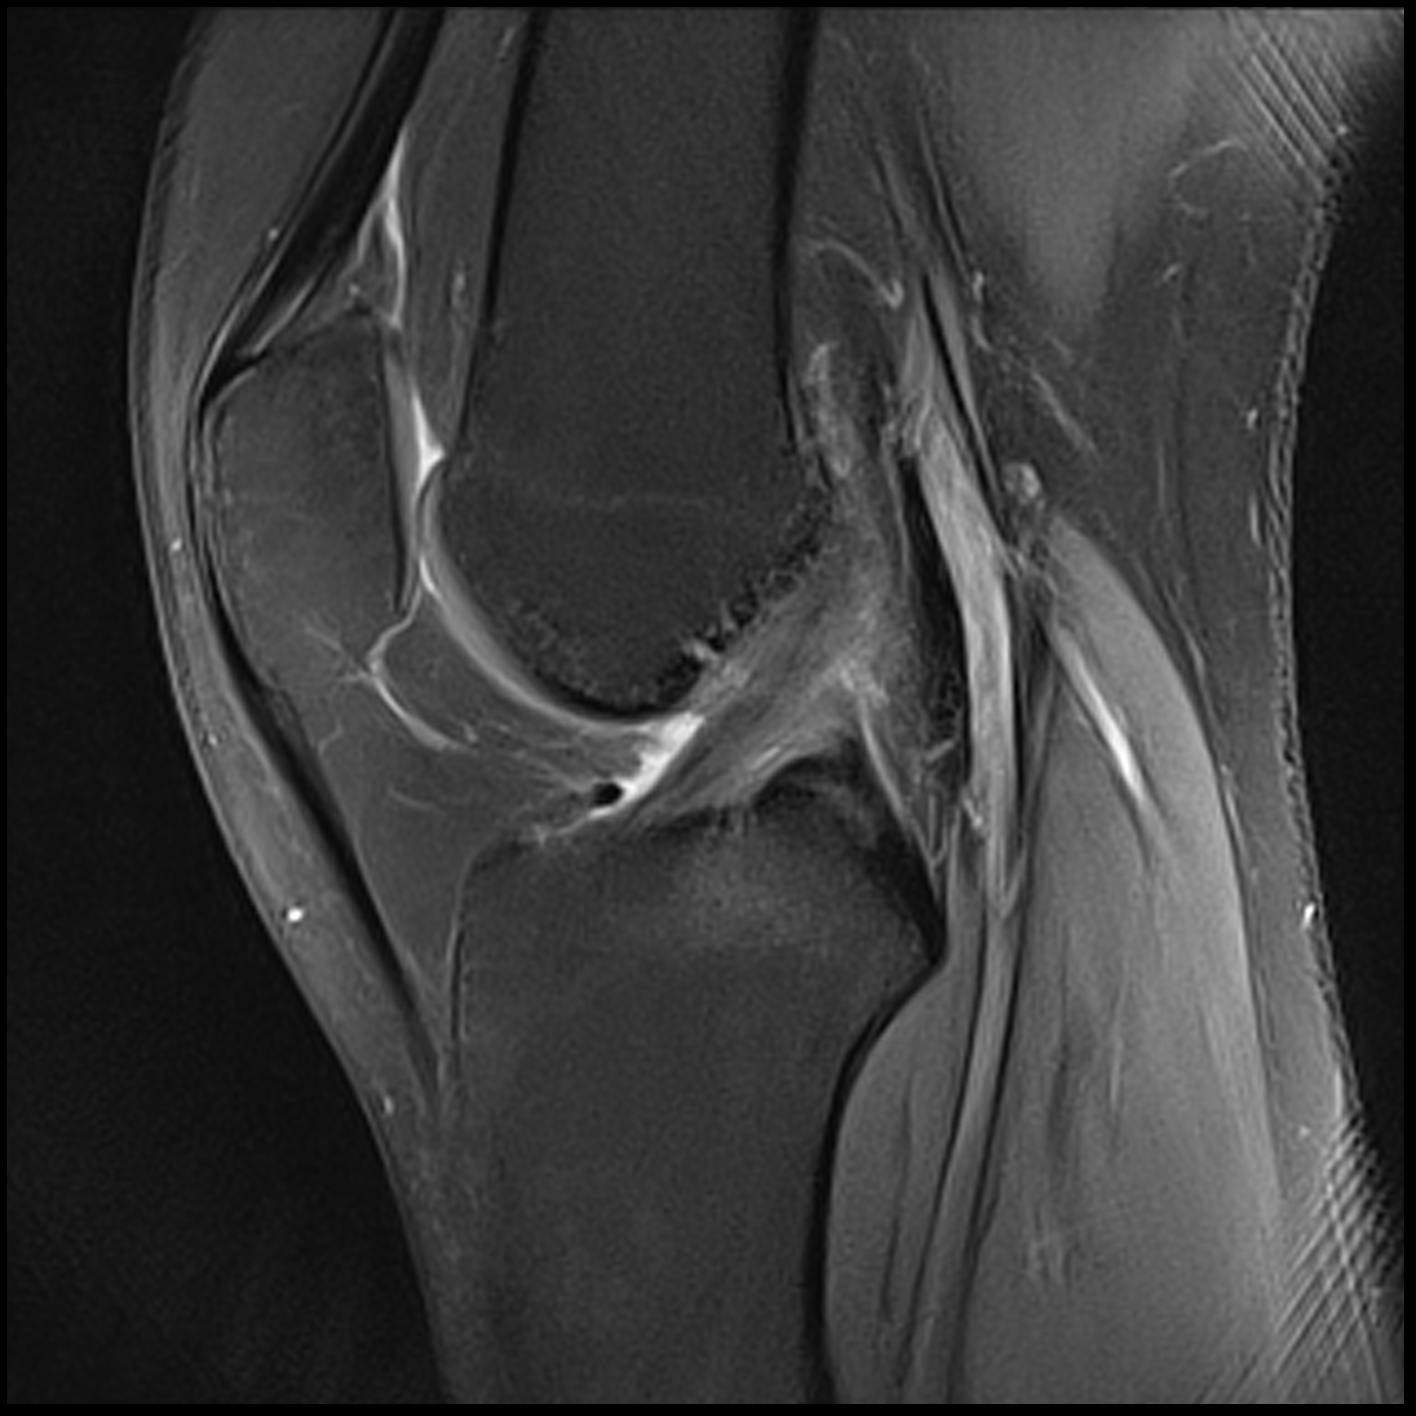

December 2019 MRI

IMPRESSION

- Medial: Nondisplaced horizontal longitudinal tear extending obliquely to the

undersurface of the meniscal body and posterior horn segments. No chondral erosion or thinning. Intact root ligaments. - Intact anterior cruciate ligament. Normal posterior cruciate ligament. Intact medial

lateral supporting structures. - No joint effusion or synovitis. No periarticular muscle injury. No osseous contusion

or stress injury. Minimal fluid in the semimembranosus-medial gastrocnemius bursa. No

frank Baker's cyst.